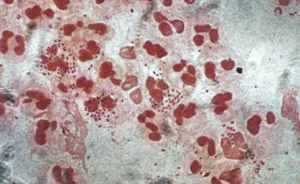

Behandlingsmuligheder for klamydia Hvordan behandler man klamydia? Behandling af klamydia er normalt enkel og effektiv. Den mest almindelige behandling er en antibiotikakur, typisk azithromycin eller